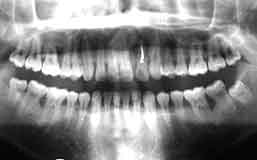

| 51歳・男性(初診時) | 初診時パノラマ |

| 「2345部にクラスプタイプの連結固定 | 下顎残存歯の全てに歯周疾患と根尖病巣による歯槽骨の破壊を認める |

初診時口腔内所見:

クラスプによる固定が施されているものの、下顎残存歯全てに動揺が認められ排膿も著明であった。

また、歯石が大量に沈着しており、全ての歯に根尖病巣が存在した。